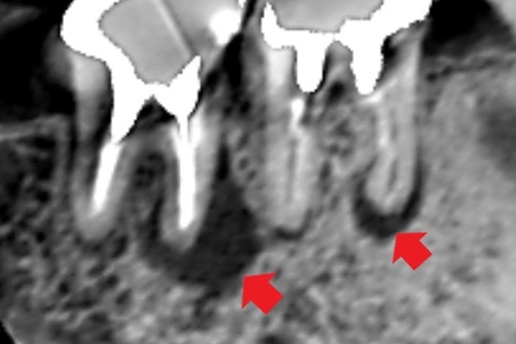

■破折歯

他院で歯が割れているため抜歯と言われたケース。当院で診断したところ破折ではないことが判明し、適切な処置で抜歯せず歯を再生させた。